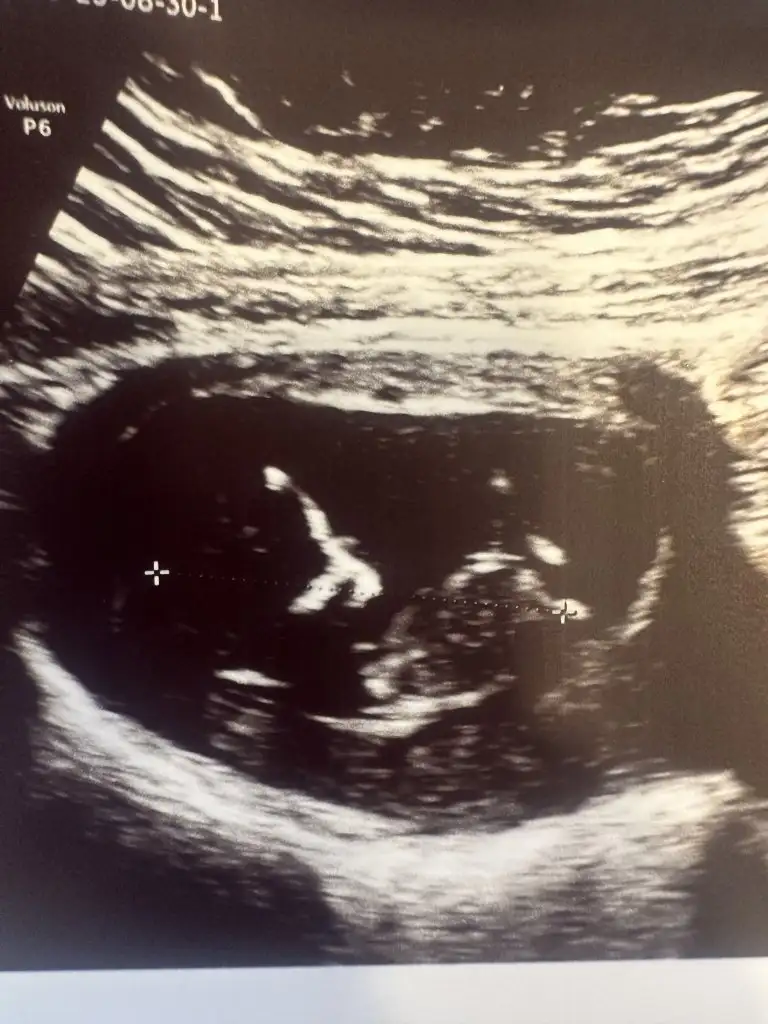

Bebek çok ortadaEki Görüntüle 3287081 karından ultrason^-^

7+4 anlayamadıysanız mühim değil yyazmanız bile mutlu ettiBebek çok ortadakaç haftalık burada

Bir tık kıza daha yakın ramziye göre bunu da diyebilirim. %53 kız diyeyim7+4 anlayamadıysanız mühim değil yyazmanız bile mutlu etti

Ahahhah çok teşekkür ederim tahmininiz içinBir tık kıza daha yakın ramziye göre bunu da diyebilirim. %53 kız diyeyim![]()